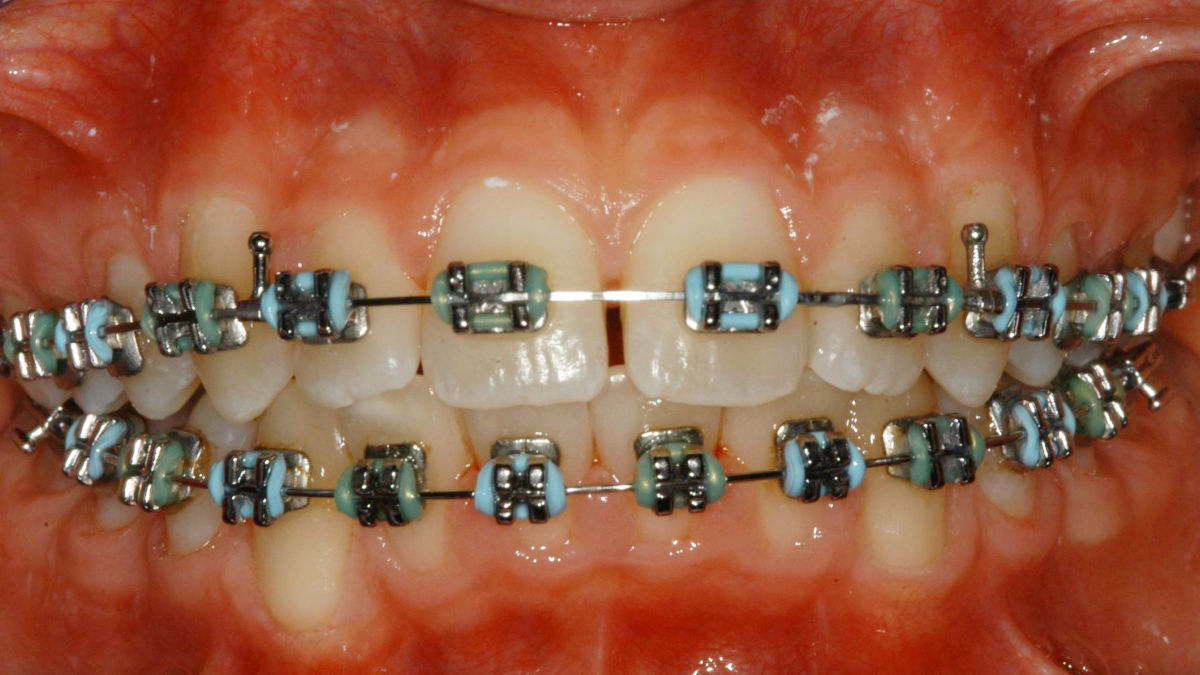

Bläser:innen sind aufgrund ihrer intensiven Nutzung des Kiefers und der Zähne in ungewöhnlichen Positionen besonders anfällig für zahnmedizinische Probleme. Die beim Spielen von Blasinstrumenten ausgeübten Kräfte können speziell bei Kindern zu einer Fehlstellung der Zähne führen. Die Universitätsklinik für Kieferorthopädie ist in diesen Fällen Ansprechpartnerin. Repetitive Bewegungen und Druckverhältnisse, die mit dem Spielen von Instrumenten verbunden sind, können Kiefergelenksprobleme verursachen, in diesen Fällen ist die Universitätsklinik für zahnärztliche Prothetik Ihre Ansprechpartnerin. Bei wiederkehrendem Lippenherpes oder Verletzungen der Lippen und Weichgewebe durch den Druck von Mundstücken bei Bläsern kann die Universitätsklinik für Zahnerhaltung und Parodontologie helfen.